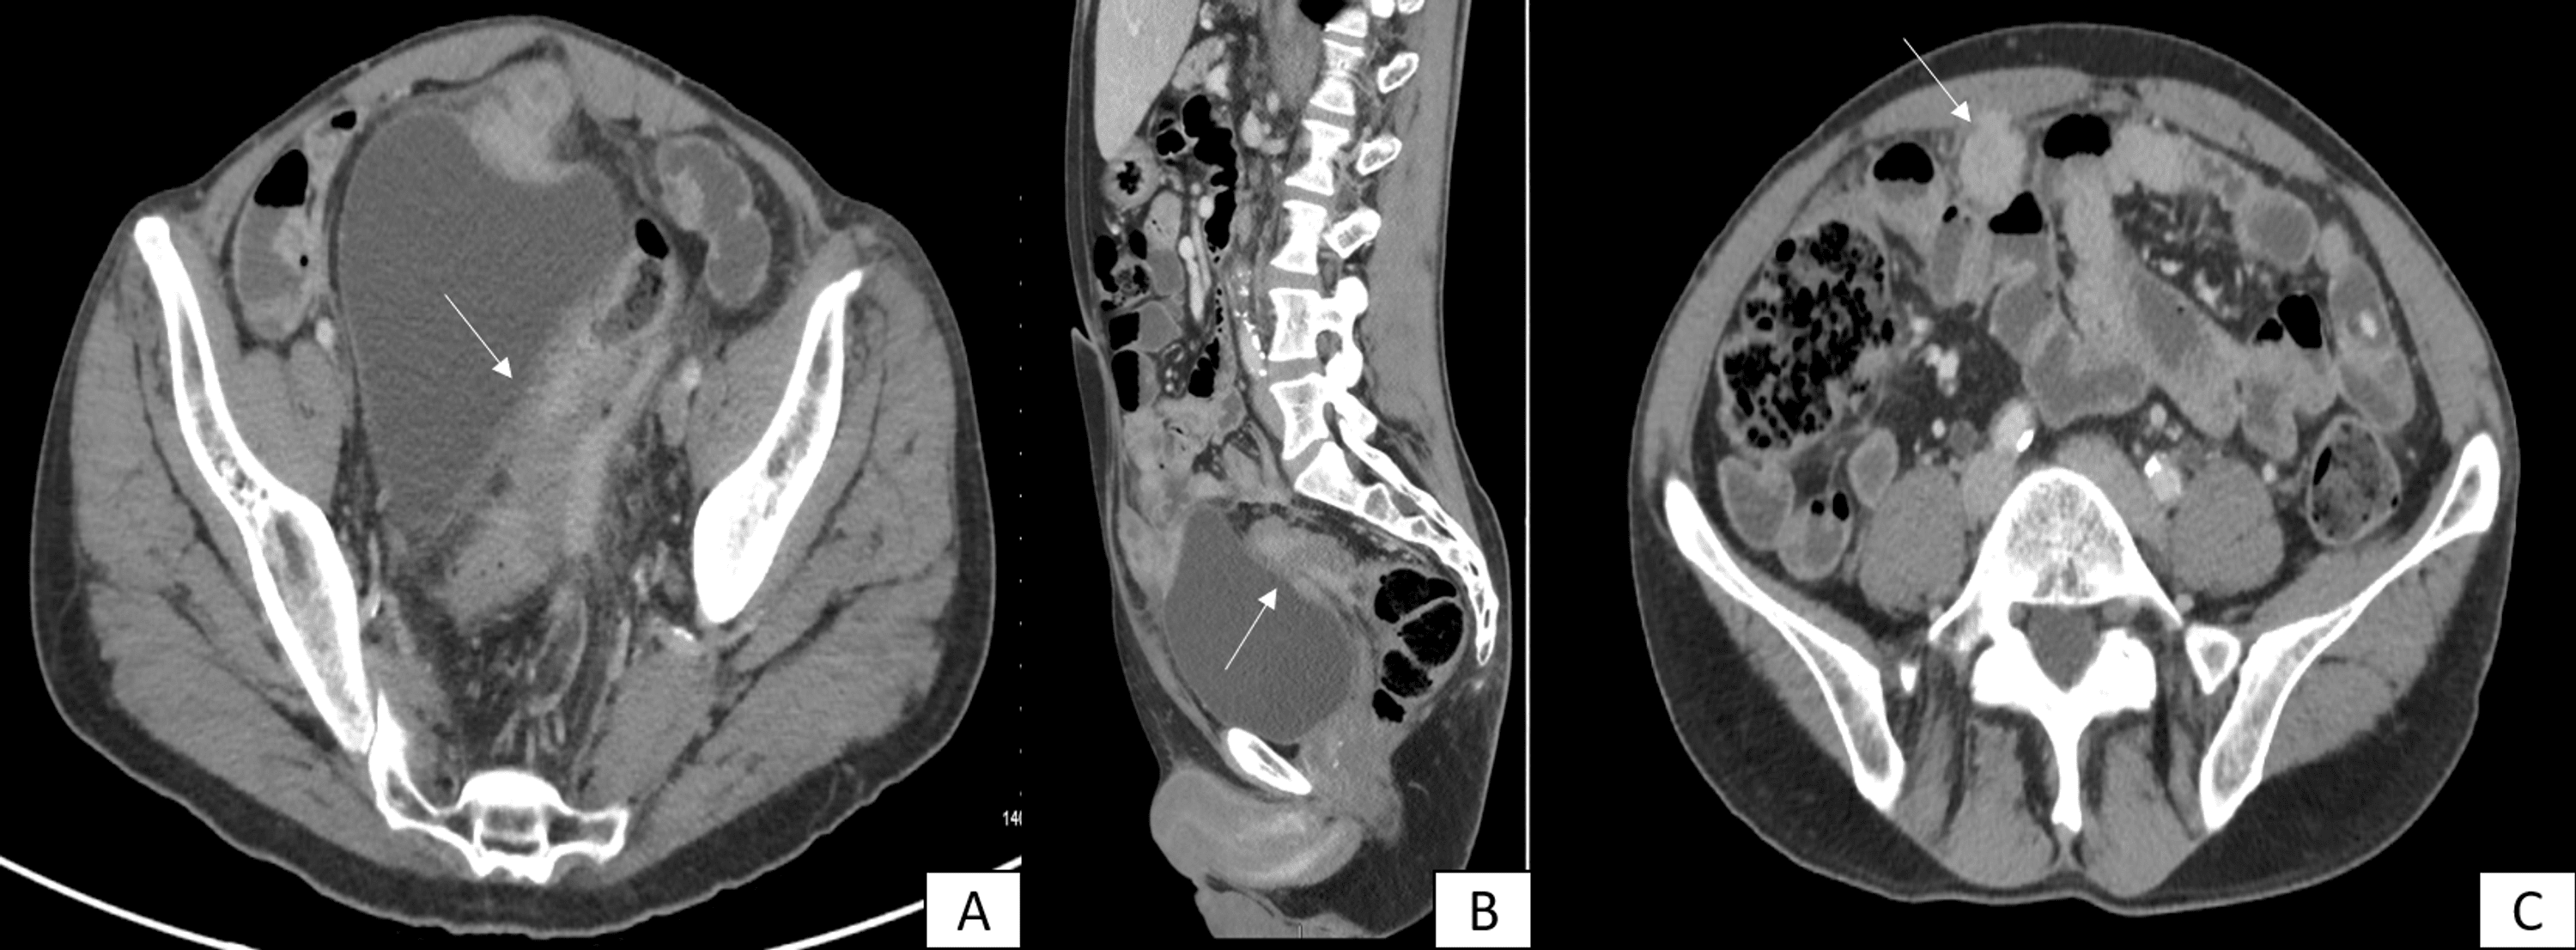

Patterns of peritoneal spread of tumor in the abdomen and pelvis

From www.wjgnet.com

Patterns of peritoneal spread of tumor in the abdomen and pelvis Abdominal Carcinomatosis Definition Peritoneal carcinomatosis is most often. Peritoneal carcinomatosis is a form of cancer that affects the peritoneum. The peritoneum is a thin membrane that covers most abdominal organs and lines the abdominal cavity. Cancer that has spread to the lining surfaces of the peritoneal (abdominal) cavity from ovarian cancer, primary colorectal cancer, appendiceal. It’s sometimes called primary peritoneal. Peritoneal cancer is. Abdominal Carcinomatosis Definition.